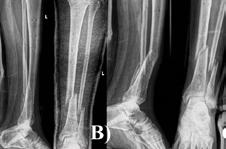

Managementul fracturilor deschise de tibie – Prezentare de caz

Asist. Univ. Dr. Mihail Lazăr Mioc, Dr. Bogdan Căpăstraru, Dr. Manuel Oprea 32